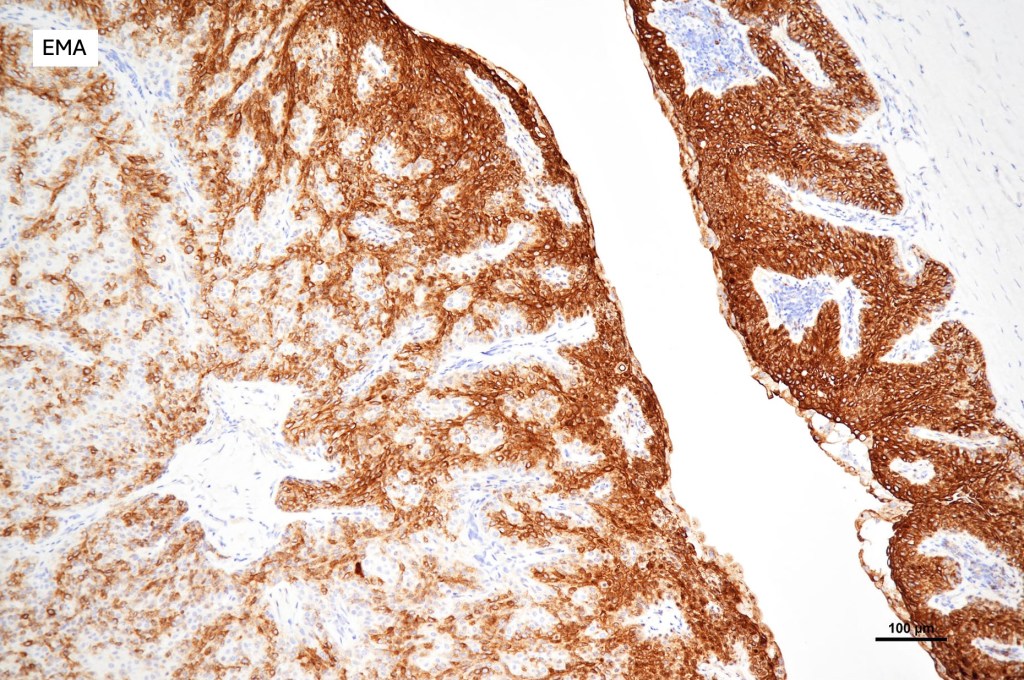

•Eccrine (predominantly poroid & cuticular cells) & apocrine variants (association with a follicle, decapitation secretion & GCDFP-15+ve)

•Ductal and glandular differentiation